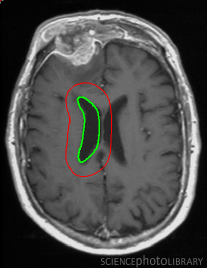

Refer to captionRefer to captionRefer to captionRefer to captionRefer to captionRefer to captionRefer to captionRefer to captionRefer to captionRefer to captionRefer to captionRefer to caption\begin{array}[]{cc}\includegraphics[width=112.0187pt]{lv-2-init.pdf}&\includegraphics[width=112.0187pt]{lv-2.pdf}\\ \includegraphics[width=112.0187pt]{lv-3-init.pdf}&\includegraphics[width=112.0187pt]{lv-3.pdf}\\ \includegraphics[width=112.0187pt]{lv-1-init.pdf}&\includegraphics[width=112.0187pt]{lv-1.pdf}\\ \end{array}

Figure 15: Segmentation of left ventricle wall of the heart in an MR image taken from [42]. Left column shows initialization and right column shows converged result.

We next develop templates for objects with hole(s) in their structure. These templates are called ring templates. Figures 15 and 16 show examples of ring templates. The area enclosed between the red contours act as region 1subscript1\Re_{1} and the area between the green contours is region 0subscript0\Re_{0}. Figure 17 shows the construction of the ring contours. The two seemingly unconnected contours are actually one connected contour. Hence, partial derivative calculations in equation (26) are still valid.

In Figure 15, the ring template has been used for segmenting the left ventricular (LV) wall of heart in cardiac MR images. Another example is shown in Figure 16. The template used in both examples has a greater thickness in the inner ring-shaped annular region than the outer annular region. This was done to facilitate obtaining the desired object’s structural information by means of the contrast (for example, between the endocardium and the LV wall) that a good initialization can offer. Hence, while designing a template, we can incorporate prior knowledge of the object and its surroundings.